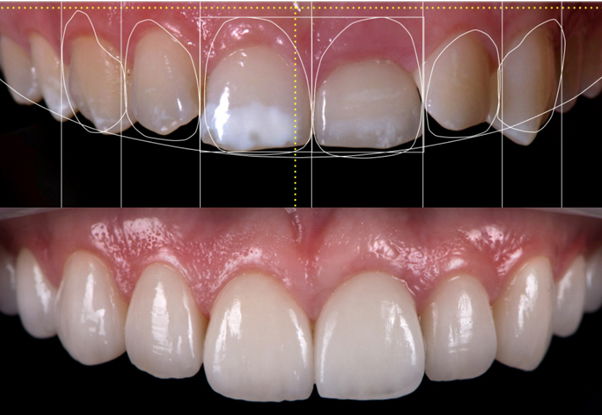

Digital Smile Designing

Digital smile design is a digital treatment planning tool that enhances diagnostic vision and improves predictability which helps to create beautiful smiles. With this we can plan treatment more effectively as a team, and perform better treatments in a more efficient way.

Cosmetic Veneers

Dental veneers are called as porcelain veneers or laminates. These are thin, custom made tooth colored shell like coverings bonded on individual teeth to alter shape, size, color and alignment of imperfect teeth. Dental veneers can be made of tooth colored composite or porcelain. Porcelain veneers are custom made cap like structures fabricated in the laboratory that are indirectly bonded to the tooth structure. Unlike porcelain veneers, composite veneers are directly bonded to the tooth surface by carefully sculpting composite on the tooth.